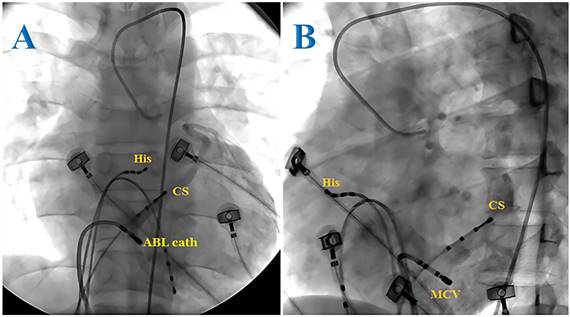

The tachycardia in most cases (72.6%) in this study was attributed to the atrioventricular accessory pathway, with 29.5% of the cases presenting with Wolff-Parkinson-White (WPW) syndrome and 43.1% of the cases with concealed accessory pathway. AVRT accounted for 27.4% of the cases and no cases of atrial tachycardia were observed. Of the 69 patients with tachycardia associated with accessory pathways, three cases (4.3%) presented with two accessory pathways. The most frequent accessory pathway locations were the left lateral (37.5%) and right lateral (23.6%) positions. In our study, 1 of 10 posterior wall accessory pathways was found to be located in the CS. In this case, after multiple unsuccessful endocardial ablation attempts in the posterior wall region, we decided to explore the CS and successfully ablated the accessory pathway. We then performed a retrograde CS angiogram and determined the ablation site to be in the middle cardiac vein (Figures 1 and 2). In patients with WPW syndrome, the most common site of the accessory pathway was the right side (33.3%), while the concealed accessory pathway was dominant in the left side (45.2%) (Table 1). Orthodromic AVRT was observed in 98.5% of the cases, with one patient showing antidromic AVRT (1.5%). The approach to the left-sided accessory pathways was through retrograde aortic access. No cases of pre-excited atrial fibrillation were detected. The average heart rate during tachycardia was 193 beats/min.

Figure 1

Radiofrequency ablation of the epicardial accessory pathway located in the coronary sinus of a pediatric patient from the anteroposterior view (A) and left anterior oblique view (B). ABL cath: ablation catheter; CS: coronary sinus; His: His bundle.

The epicardial accessory pathways related to the coronary sinus (CS) occupy approximately 19-33% of the atrioventricular pathway and may be located in the CS ostium, proximal CS, or CS diverticulum [11]. CS injury due to ablation should be considered, and, therefore, CS angiography is recommended. In Müller's study, the overall success rate of CS ablation was 90.9%, with a CS injury rate of 9%, and 23% of patients experienced recurrence of PSVT after an 8.4-year follow-up [12].